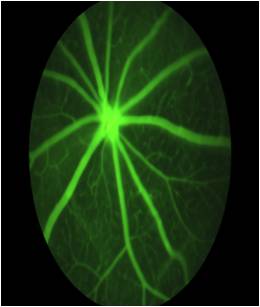

实验动物技术平台配备了手术显微镜、前节照相、动物电生理等科研仪器设备,可提供生理学、影像学、行为学分析等相关技术支持。并有专业负责人提供实验室技术支持以及实验前准备,包括动物申领购买、实验所需耗材购买、实验器械和实验场地消毒、仪器调试等。